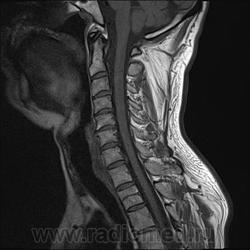

Шейный остеохондроз.Грыжа С7-Th1.Не исключено наличие миелопатии на этом уровне, но боюсь ошибиться-изображения мелковаты ,идаже кажется, что есть повышение МРС от спинного мозга по Т1( скорее всего-артефакты?).

Левосторонняя парамедианная с компрессией корешка.

а это не перидурит??? смотрели месяц назад (в начале заболевания) было меньше.

Посмотрите на STIRе. Если жидкости нет, то простая грыжа. На этих сканах вообще-то жидкости не видно. За месяц грыжа могла и подрасти, смотря как лечили.

По-моему, только грыжа.